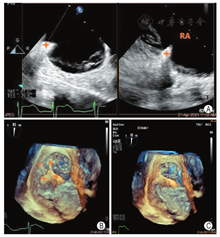

手术过程:患者于复合手术室取平卧位,常规消毒铺巾,静脉复合麻醉后。①穿刺左侧桡动脉监测血压,穿刺右侧股动脉/股静脉分别置入6F/6F鞘管,右冠状动脉造影正常,然后于右冠状动脉内放置冠状动脉导丝(ASAHI SION PTCA Guide wire,0.014″×180 cm)以标记右冠状动脉与三尖瓣后瓣环的空间位置关系。②穿刺右侧颈内静脉,预置1把ProGlide后,穿刺置入9F鞘管,然后进入Amplatz Superstiff (Amplatz Superstiff J Tip Guider wir,0.035′×260 cm)导丝,并在二维(2D)TEE食管中段上下腔切面监测下将导丝置入下腔静脉入口处(图3),退出9F鞘管,将18F K-clip可调弯鞘(下称大鞘)在2DTEE和(或)三维(3D)TEE食管中段上下腔切面监测下缓慢推进至右房中下部(图4),并固定于无菌床头固定器上。③沿大鞘进入K-Clip可调弯输送系统至大鞘末端并后撤大鞘4~5 cm,在2DTEE、3DTEE及DSA引导下调整K-Clip输送系统至三尖瓣瓣环前后叶交界处(图5),并拧入固定螺丝,张开K-Clip夹合臂并调整夹合臂方向与三尖瓣瓣环切线平行,进行夹合(图6,图7)。④夹合术后即刻彩色多普勒显示TR程度由5+(极重度)减少至2+(中度)(图8),连续多普勒记录三尖瓣平均跨瓣压差为1 mmHg,3DTEE描记三尖瓣瓣口面积由术前8.50 cm2减少至5.33 cm2(图9),2DTEE检查无瓣叶损伤及心包积液,冠状动脉造影提示RCA中远端50%左右压迫狭窄,前向血流TIMI 3级,此时患者血压为116/70mmHg,心率为70次/min,基本平稳,逐释放K-Clip夹合器,撤出输送系统并退出大鞘,ProGlide血管缝合右侧颈内静脉,手术完成。

术后5 d患者一般情况尚可。TEE显示:K-Clip夹合术后,中重度TR,下腔静脉内径由术前19 mm缩小至16 mm(随呼吸塌陷率约15%),左室收缩功能未见异常(LVEF:62%)(图10)。